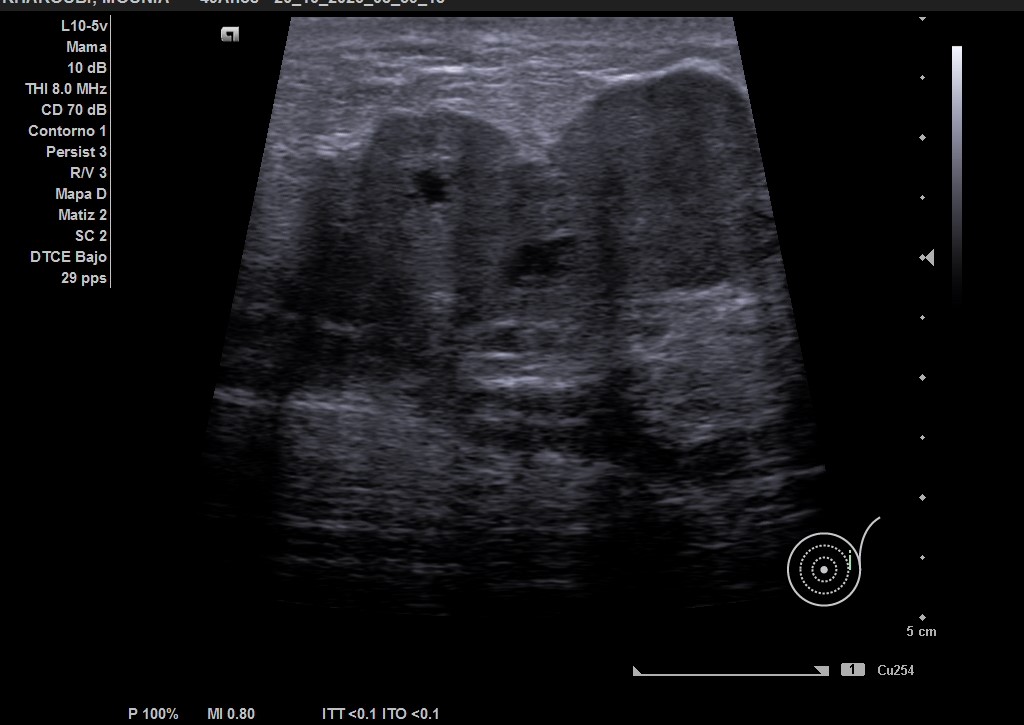

Hallazgos ecográficos

Ecografía: mama izquierda se observa tumoración hipoecogénica lobulada en cuadrante superior externo de aproximadamente 4 cm, heterogénea, que capta al Doppler color y dos adenopatías de aspecto reactivo en axila homolateral. Imagen sospechosa de malignidad.